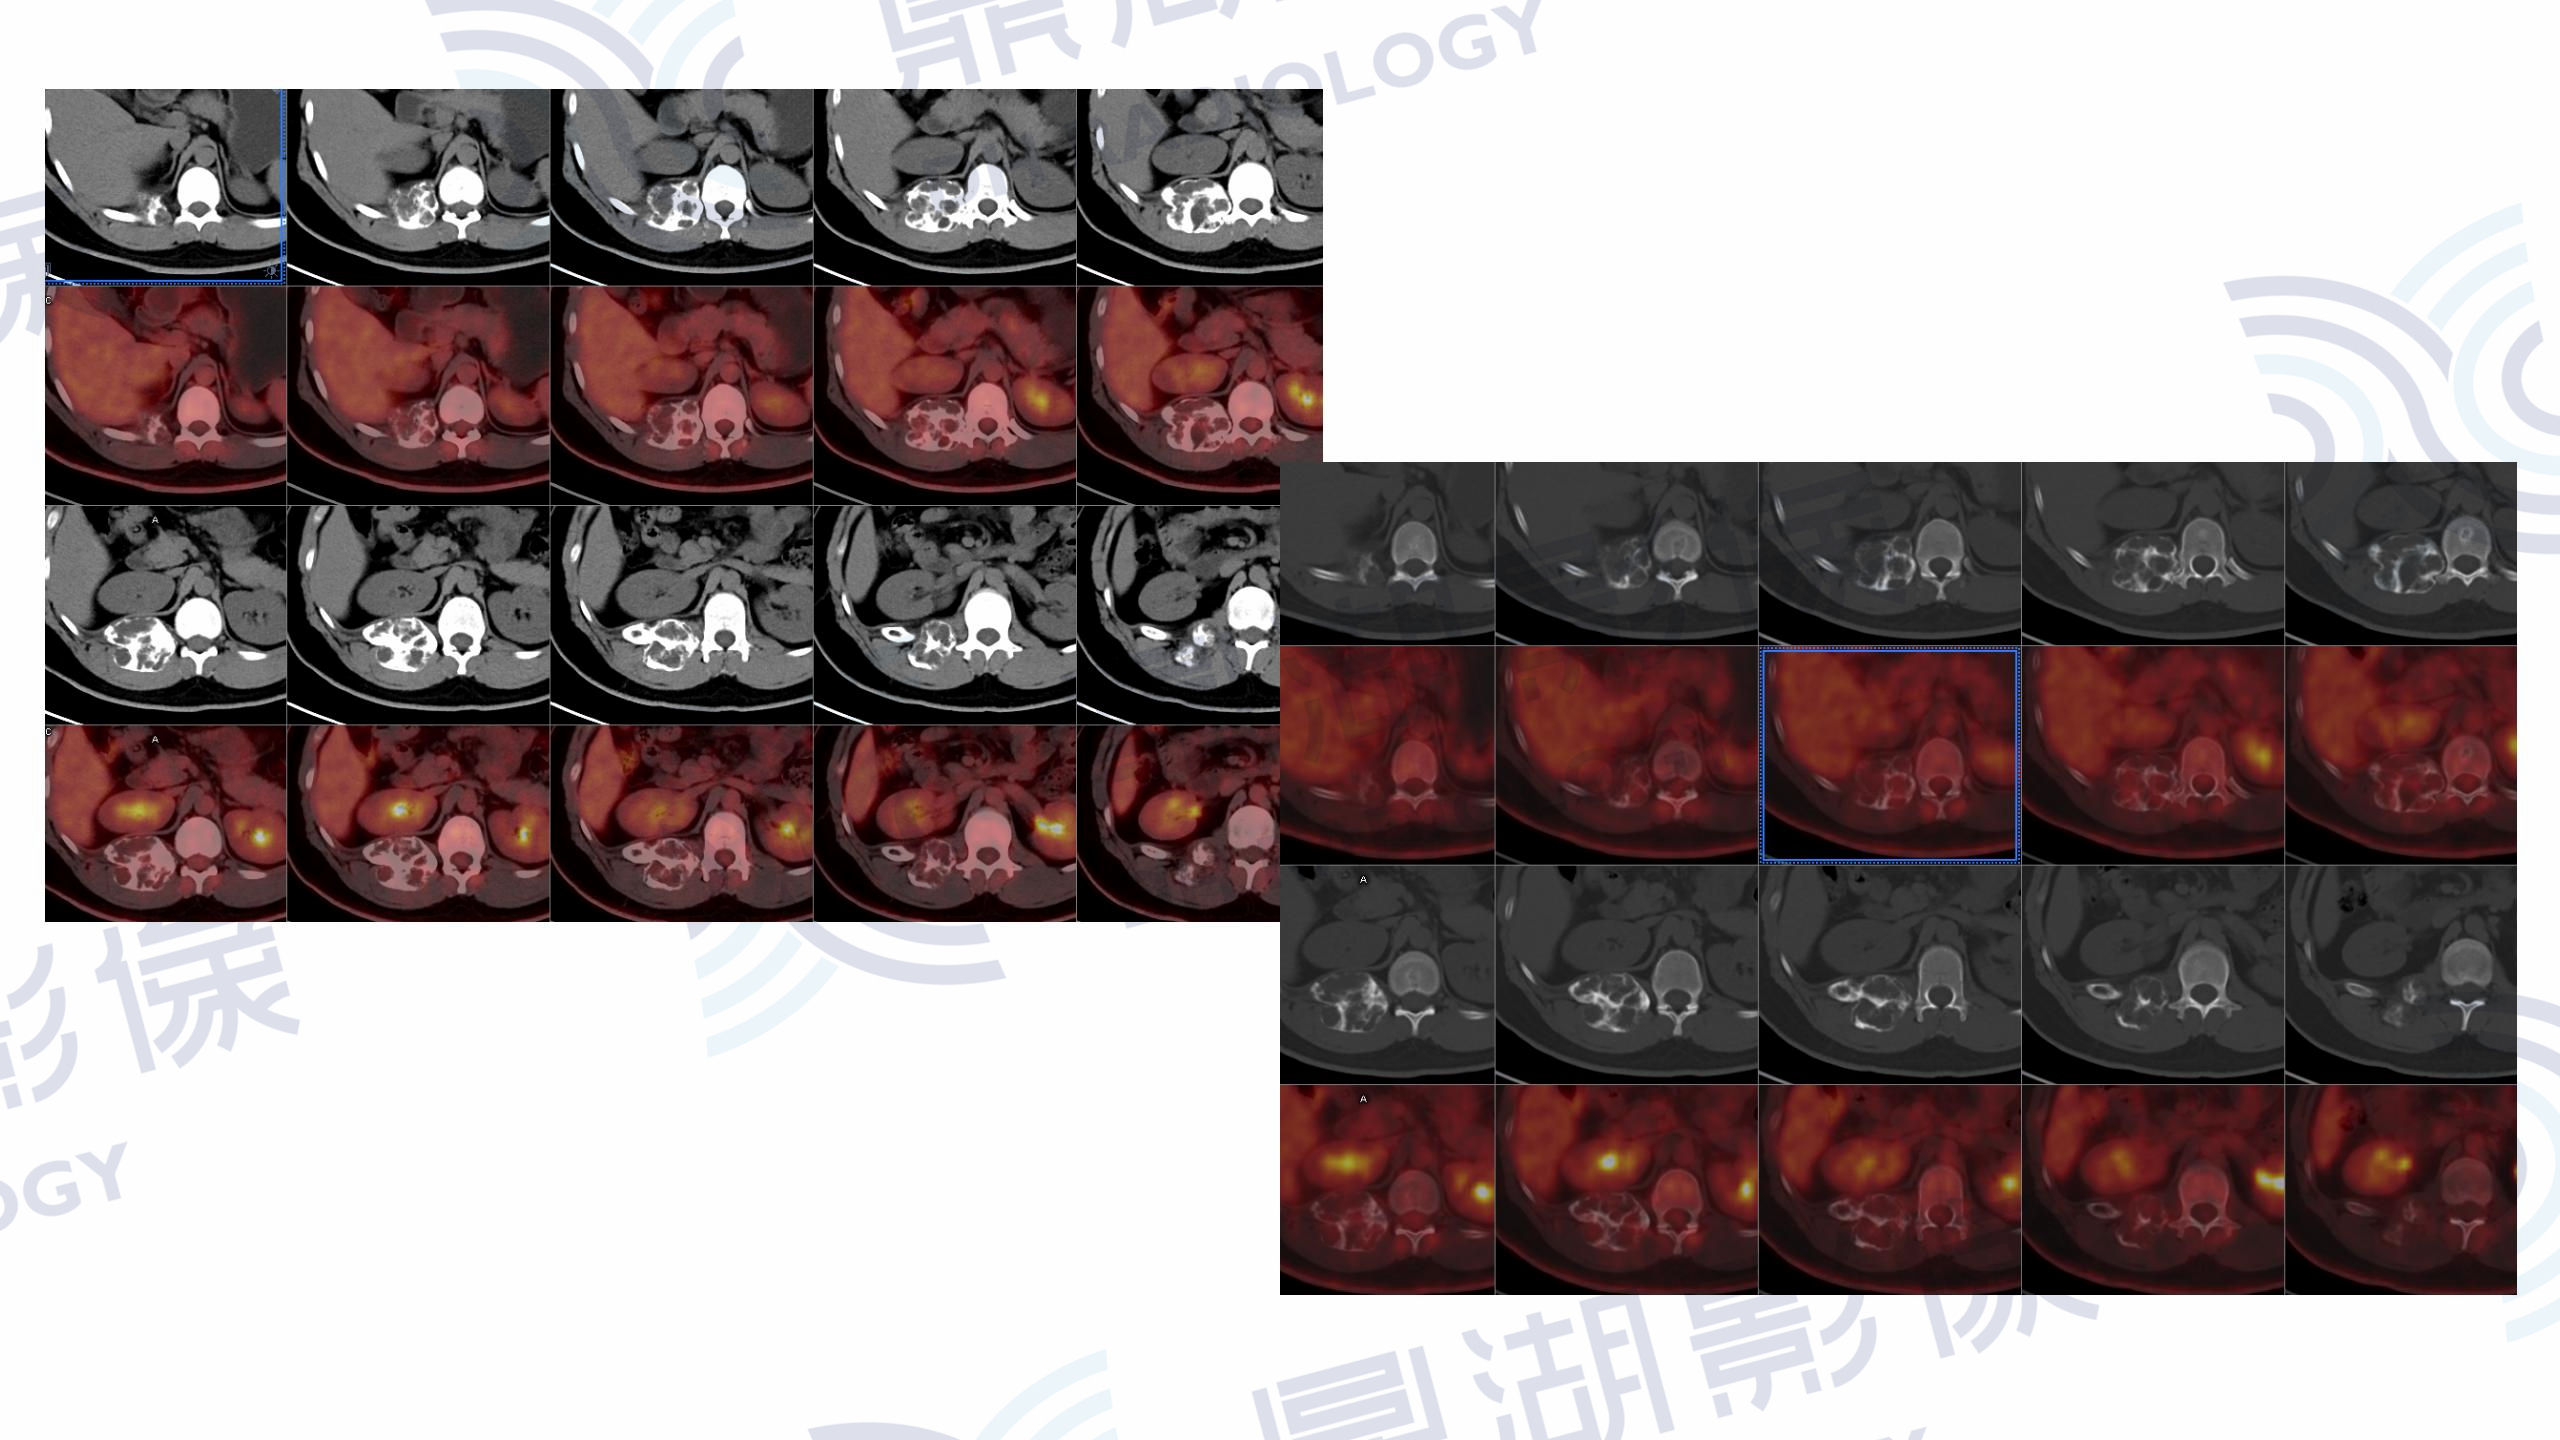

肋骨上皮样血管瘤

CT

PET

性别:男

年龄:50

主诉:背痛2月余

背痛2月就诊,外院CT扫描提示,发现肋骨病变。肿瘤标志物无异常。